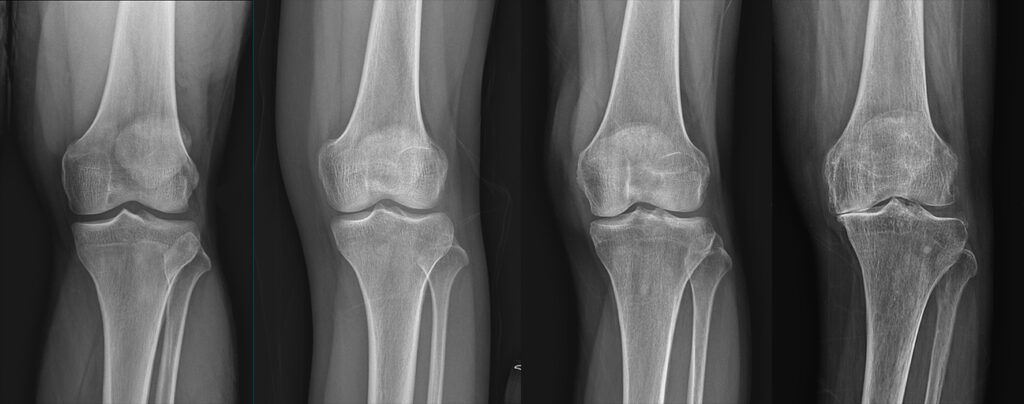

활막에 염증이 생기면 주변 연골과 뼈로 염증이 확산되며 관절 통증, 열감, 압통과 함께 부종이 발생합니다. 보통 양측성으로 나타나며 손목·팔꿈치·무릎·손가락·발가락 등에서 흔히 통증을 호소합니다.

5. 관절 붓기

평소보다 손발이 붓거나 신발이 갑자기 꽉 끼는 느낌이 든다면 관절 내 염증과 관절액 증가를 의심해 볼 수 있습니다. 활막 부종과 관절 삼출이 반복되면 연골과 주변 조직이 손상되어 관절 변형이나 운동 제한이 생길 수 있으므로 초기에 꾸준한 치료가 중요합니다.